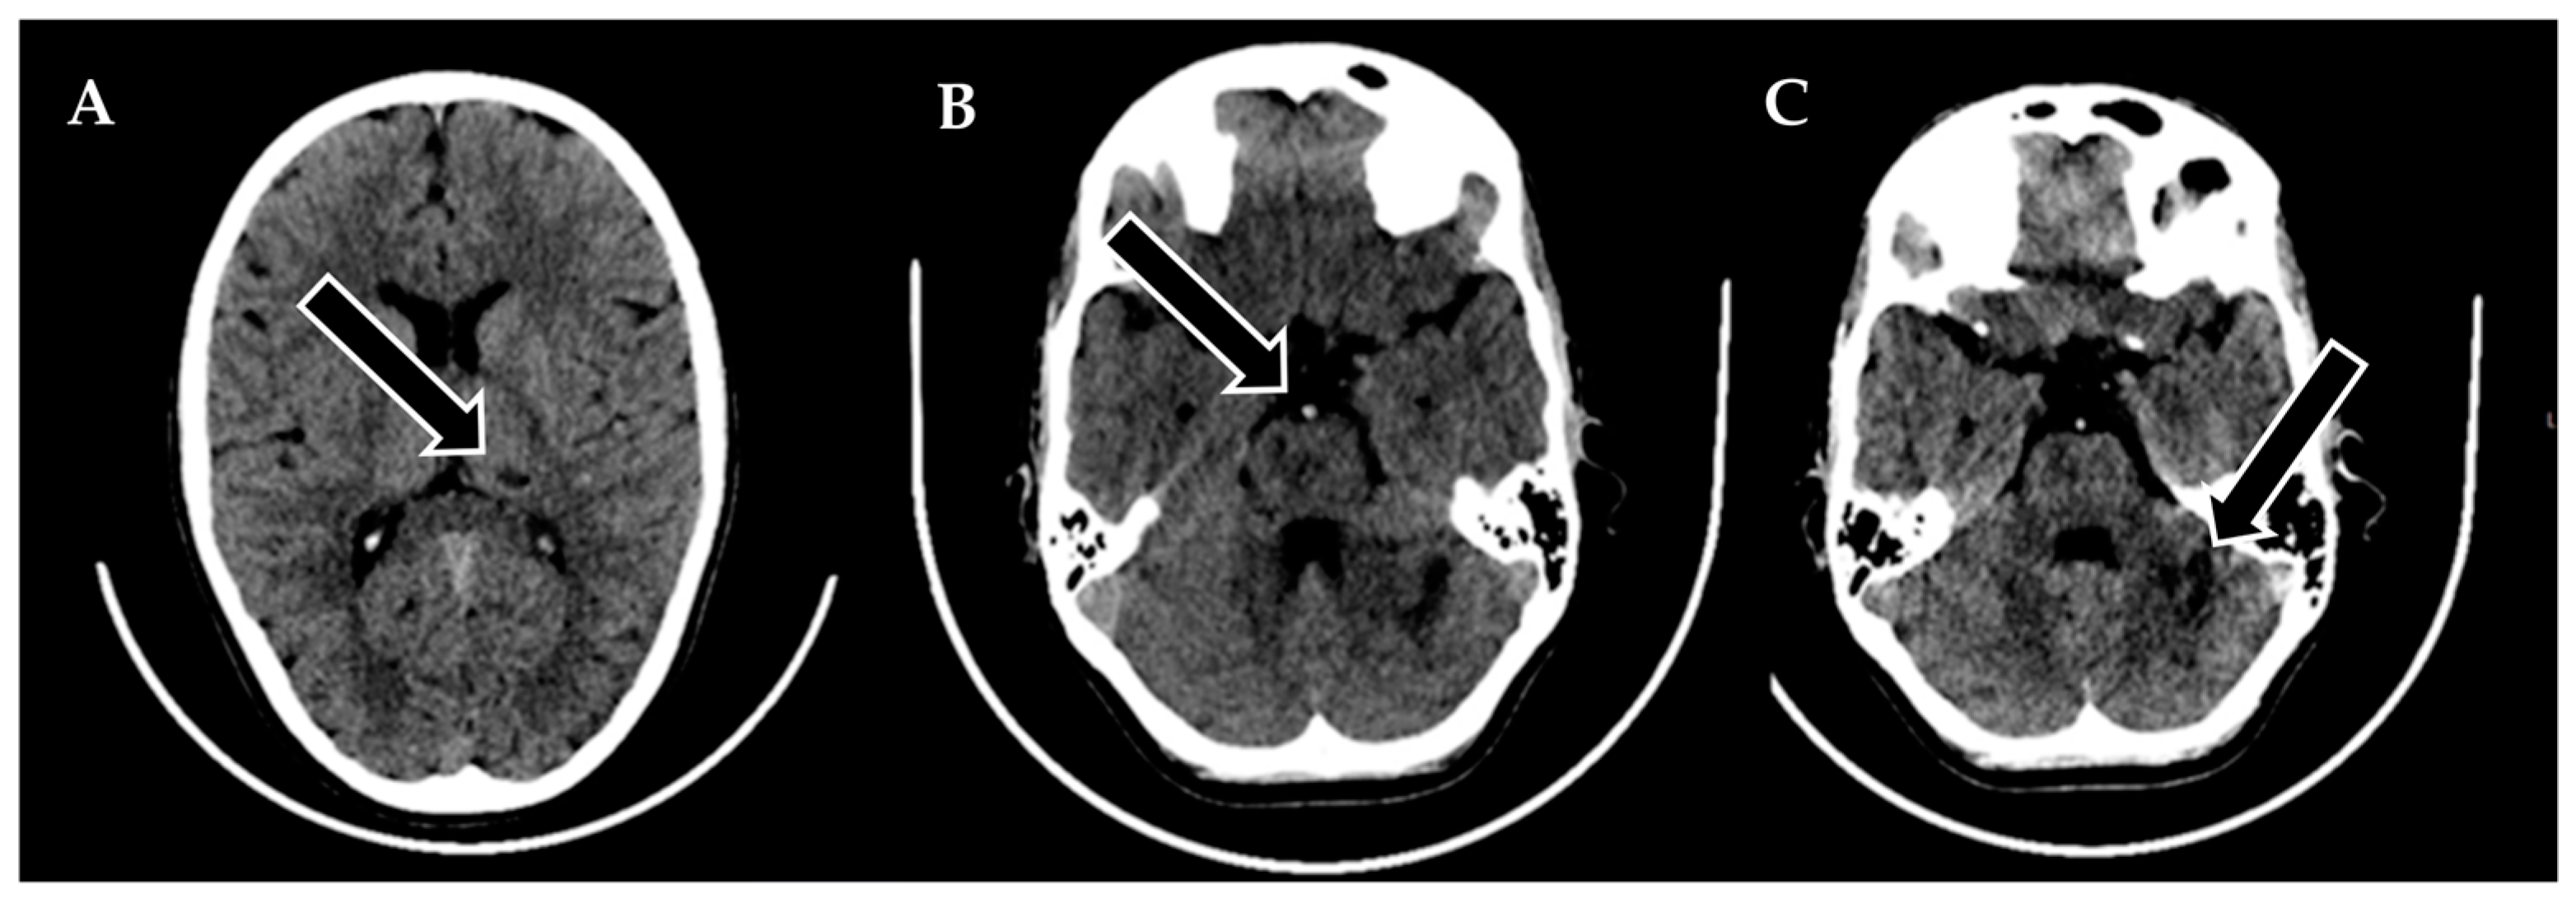

Following 3.5 h and in consultation with a pediatric specialist, the decision was made to transfer the patient to the Children’s Clinical University Hospital for a more comprehensive diagnostic assessment. An emergency magnetic resonance imaging (MRI) was conducted (Figure 2), revealing acute ischemia within the vascularization area supplied by the left posterior inferior cerebellar artery (PICA). Moreover, this MRI also indicated involvement in regions supplied by the left anterior inferior cerebellar artery (AICA) and superior cerebellar artery (SCA). The magnetic resonance angiography (MRA) performed concurrently showed evidence of a thrombus causing occlusion in the distal one-third of the basilar artery (BA). This comprehensive imaging assessment illuminated the extent of the vascular compromise and provided critical information for further evaluation and treatment planning.

Figure 2. Emergency magnetic resonance imaging (MRI) before intervention. (A) Changes in the ADC map seen in the left PICA, as well as slightly in the AICA and SCA regions; (B) diffusion-weighted images showing acute changes in the left PICA, as well as slightly in the AICA and SCA regions; (C) MRA showing stop of flow in the distal 1/3 of the basilar artery.